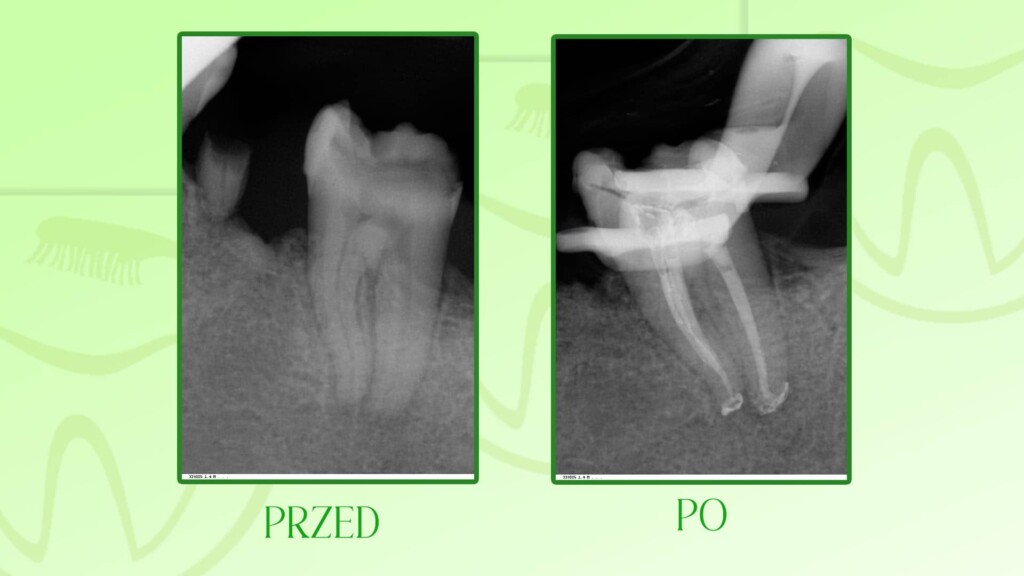

Poniżej prezentujemy wybrane prace leczenia kanałowego zębów wykonane w naszym gabinecie dentystycznym Unident w Szczecinie